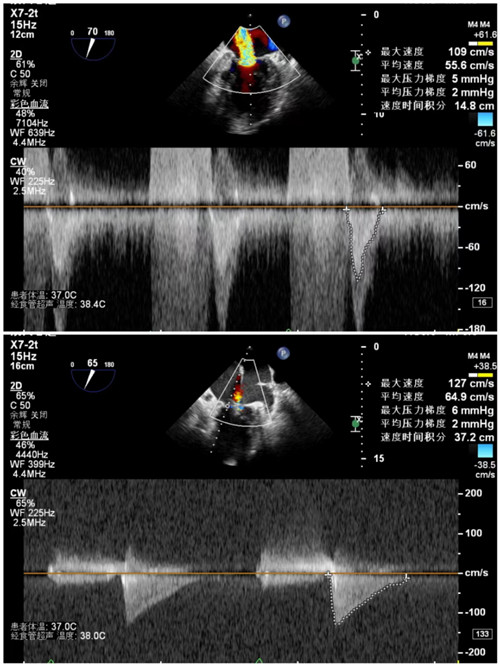

手术前后二尖瓣压差

7月9日上午,心内科联合麻醉科、胸外科等多学科,共同为陈奶奶开展手术,术前二尖瓣大量反流,反流程度5+,肺静脉反流明显,术后二尖瓣少量反流,反流程度1+,肺静脉反流消失,手术顺利结束。术后安返病房,次日陈奶奶从不能平卧到能下床活动。在医护人员的精心照顾下,陈奶奶现已顺利出院。